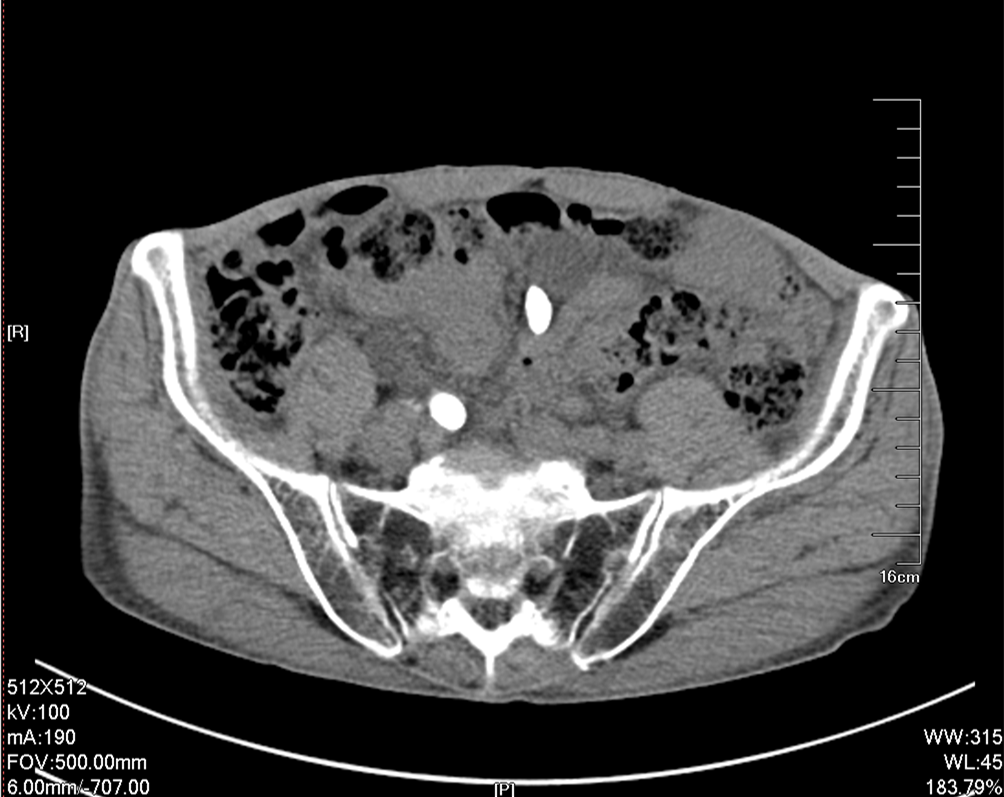

入院后行双侧经皮肾穿刺造瘘术,保护肾功能,十天后Cr下降至236umol/L,顺行造影检查发现双侧输尿管迂曲扩张明显,双侧输尿管结石完全梗阻,造影剂无法进入膀胱。